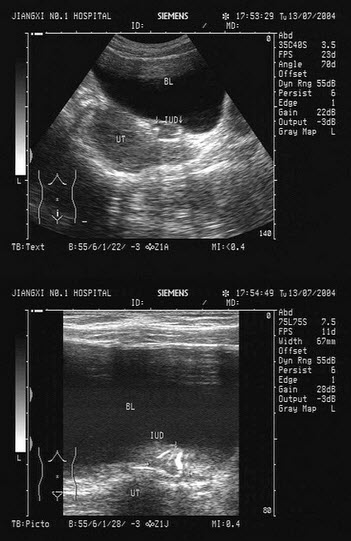

女性,48岁,取环术后3天,述左下腹疼痛。B超检查如图,最可能的诊断为()

A.畸胎瘤

B.盆腔血肿

C.子宫浆膜下肌瘤

D.宫外孕

E.附件囊肿

119、单项选择题